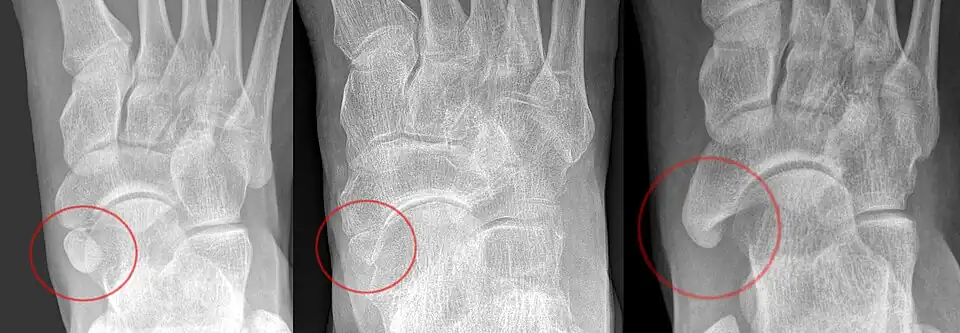

The Geist classification divides the accessory navicular bones into three types.[3]

- Type 1: An os tibiale externum is a 2–3 mm sesamoid bone in the distal posterior tibialis tendon. Usually asymptomatic.

- Type 2: Triangular or heart-shaped ossicle measuring up to 12 mm, which represents a secondary ossification center connected to the navicular tuberosity by a 1–2 mm layer of fibrocartilage or hyaline cartilage. Portions of the posterior tibialis tendon sometimes insert onto the accessory ossicle, which can cause dysfunction, and therefore, symptoms.

- Type 3: A cornuate navicular bone represents an enlarged navicular tuberosity, which may represent a fused Type 2 accessory bone. Occasionally symptomatic due to bunion formation.

-

From left to right: Type 1, 2 and 3 -